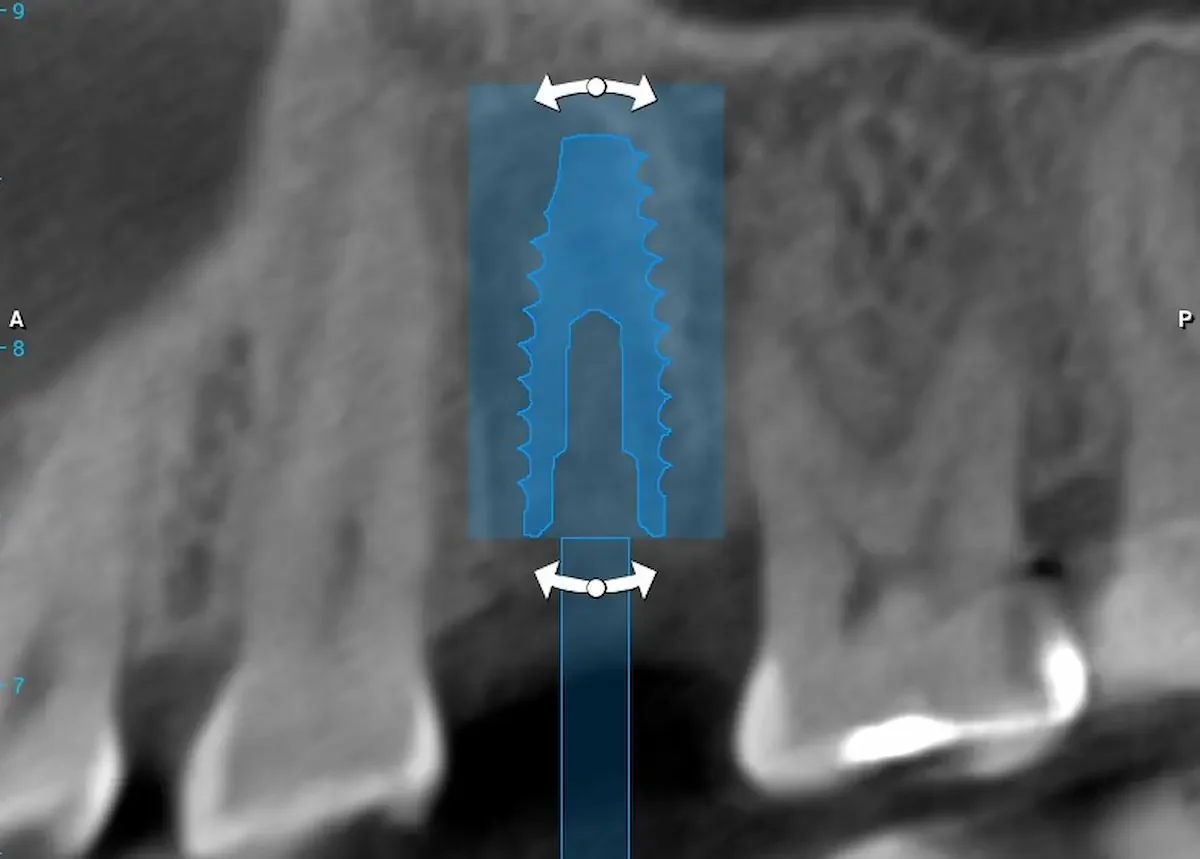

At Teuscher Legacy Dental, every implant case is planned with 3D cone beam CT imaging and digitally designed surgical guides — the same technology used by other leading surgical centers.

Visualize bone quality, and sinus anatomy, and nerve locations

Place implants with extreme precision

Often shorten healing time and improve comfort

Optimize location of future crown (the chewing part of the implant)

This first step also helps make sure the patient is on the same page with what to expect a final result to look like. We also go over financial details and timeline. This way the patient knows what to expect every step of the way!CBCT 3D Planning

CBCT (3‑D imaging) is used to assess bone quantity and quality and check for any sinus or nerve issues. There should be an evaluation of overall health (e.g., diabetes, smoking, medications) and other risk factors. Gum health should also be assessed (are there active gum infections?) and whether bone grafting is needed.Use of guided surgical planning

Digital planning and surgical guides help dentists place implants at the right angle, depth, and position, avoid critical anatomy (sinus, nerves), and preserve bone and soft tissue.Strict surgical protocol and sterile technique

Why it matters: The foundation of a successful implant starts with precision planning. During your consultation, our doctors use a cone-beam CT (CBCT) scan to create a 3D model of your teeth, bone, and jaw structure.

CBCT imaging allows us to measure bone density, identify vital structures (like nerves and sinuses), and plan the exact position of your future implant.

Using digital treatment planning, we design a custom surgical guide to ensure the implant is placed with millimeter accuracy.